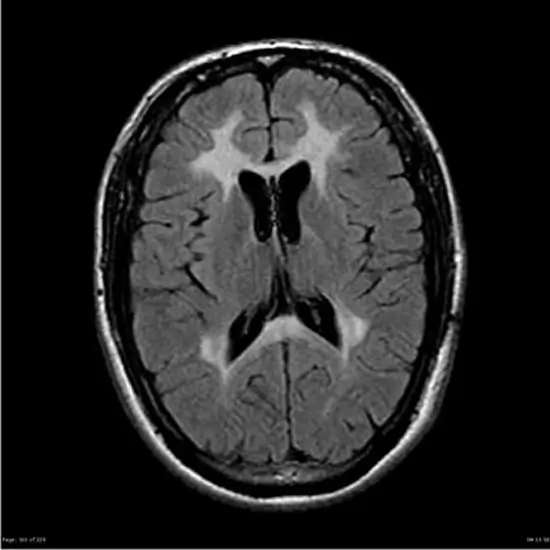

Metachromatic leukodystrophy is an inherited disorder characterised by sulfatide accumulation in cells. This accumulation has a particular impact on nervous system cells that produce myelin, the substance that insulates and protects nerves. White matter is a tissue made up of nerve cells covered in myelin. Sulfatide accumulation in myelin-producing cells leads to progressive destruction of white matter (leukodystrophy) throughout the nervous system, including the brain and spinal cord (the central nervous system), as well as the nerves that connect the brain and spinal cord to muscles and sensory cells that detect sensations such as touch, pain, heat, and sound (the peripheral nervous system).